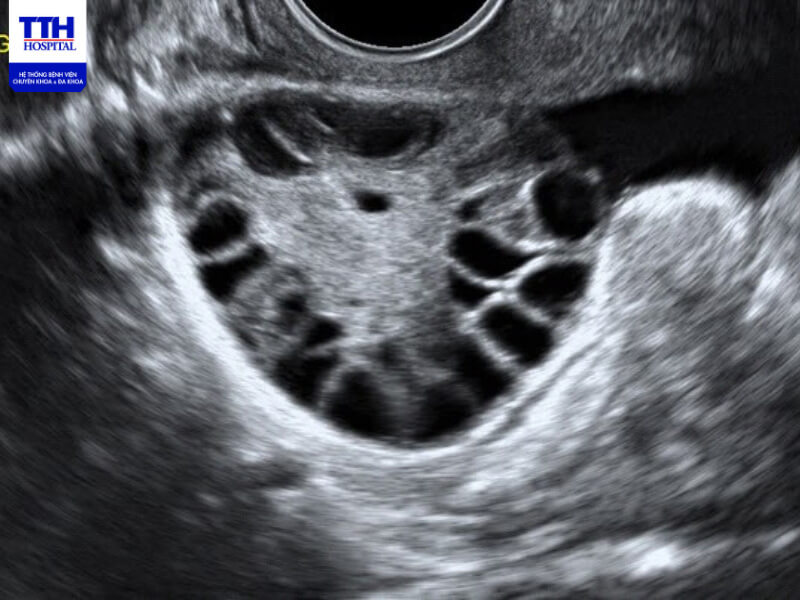

Hình ảnh buồng trứng đa nang được phát hiện trong siêu âm